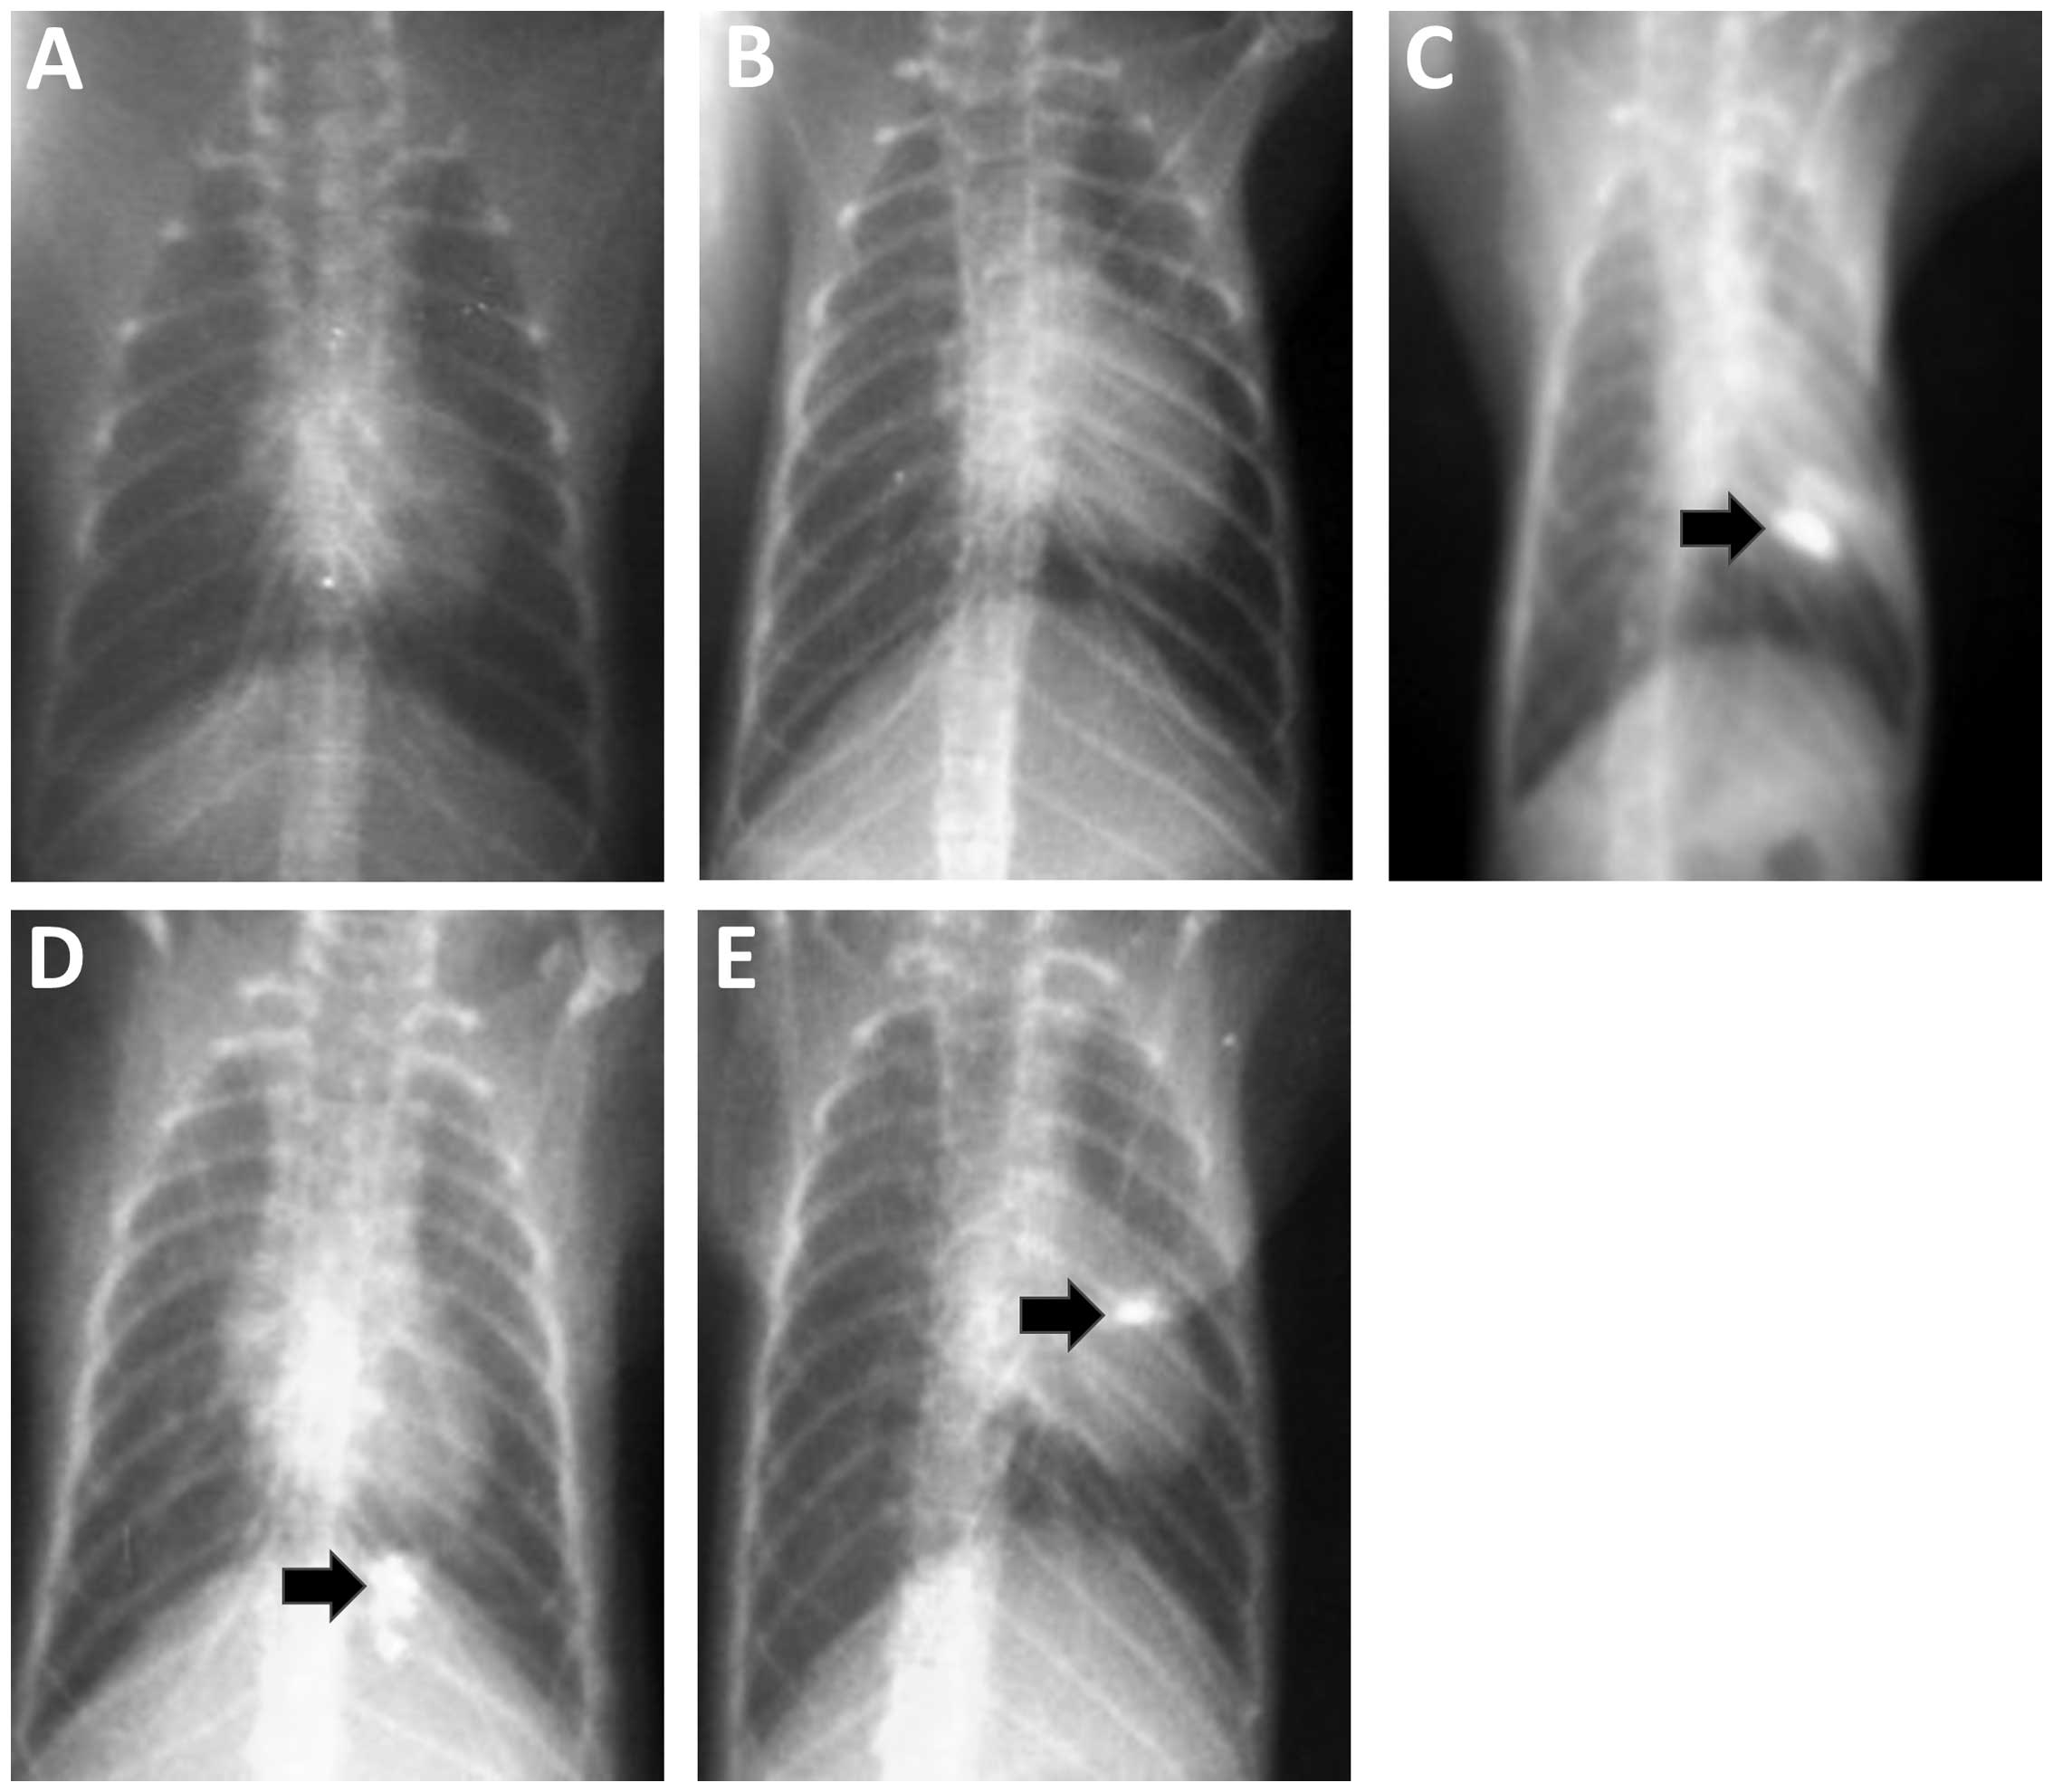

The results from the chest X-ray examinations conducted on animals in the blank control and solvent control groups at each time point revealed no obvious abnormalities (Fig. 1A and B). In the experimental group, the chest X-ray examination results for tree shrews in the 3rd, 7th and 11th weeks after perfusion showed focals of high-density shadow spots within the perfusion sites (Fig. 1C and E). We considered these high-density shadows to be the product of lipiodol incomplete metabolism. Pathological studies, performed on the high-density areas, confirmed changes in the bronchial epithelium.

Figure 1.

Chest X-rays showing changes in the lungs of tree shrews. (A) Eleventh week X-ray image from an animal in the blank control group. (B) Eleventh week X-ray image from an animal in the solvent control group; (C) third week X-ray image from an animal in the experimental group. (D) Seventh week X-ray image from an animal in the experimental group. (E) Eleventh week X-ray image from an animal in the experimental group.